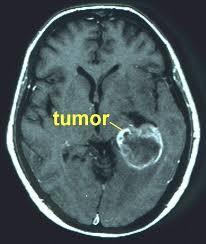

Se refiere al crecimiento anormal de células organizadas en forma atípica, que crecen a expensas del organismo pero que no cumplen un propósito dentro de éste. (2)